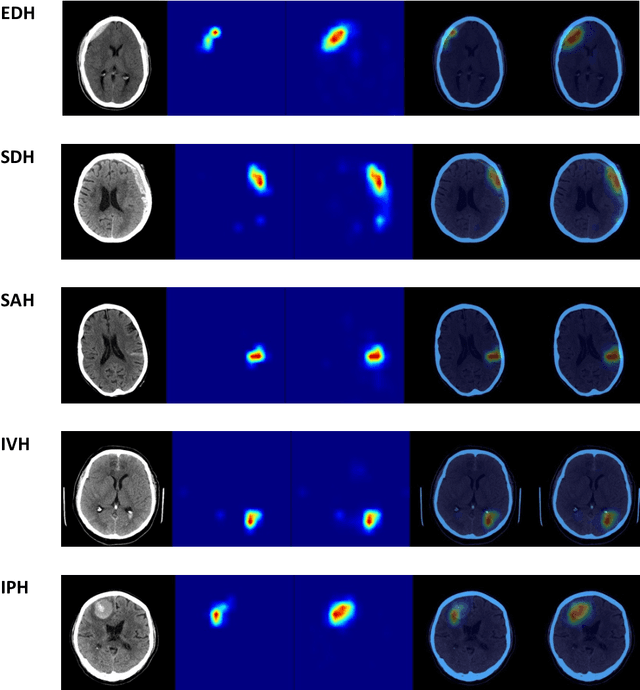

Abstract:Purpose: The purpose of this study was to determine if an ensemble of multiple LLM agents could be used collectively to provide a more reliable assessment of a pixel-based AI triage tool than a single LLM. Methods: 29,766 non-contrast CT head exams from fourteen hospitals were processed by a commercial intracranial hemorrhage (ICH) AI detection tool. Radiology reports were analyzed by an ensemble of eight open-source LLM models and a HIPAA compliant internal version of GPT-4o using a single multi-shot prompt that assessed for presence of ICH. 1,726 examples were manually reviewed. Performance characteristics of the eight open-source models and consensus were compared to GPT-4o. Three ideal consensus LLM ensembles were tested for rating the performance of the triage tool. Results: The cohort consisted of 29,766 head CTs exam-report pairs. The highest AUC performance was achieved with llama3.3:70b and GPT-4o (AUC= 0.78). The average precision was highest for Llama3.3:70b and GPT-4o (AP=0.75 & 0.76). Llama3.3:70b had the highest F1 score (0.81) and recall (0.85), greater precision (0.78), specificity (0.72), and MCC (0.57). Using MCC (95% CI) the ideal combination of LLMs were: Full-9 Ensemble 0.571 (0.552-0.591), Top-3 Ensemble 0.558 (0.537-0.579), Consensus 0.556 (0.539-0.574), and GPT4o 0.522 (0.500-0.543). No statistically significant differences were observed between Top-3, Full-9, and Consensus (p > 0.05). Conclusion: An ensemble of medium to large sized open-source LLMs provides a more consistent and reliable method to derive a ground truth retrospective evaluation of a clinical AI triage tool over a single LLM alone.

Abstract:Machine learning (ML) holds great promise in transforming healthcare. While published studies have shown the utility of ML models in interpreting medical imaging examinations, these are often evaluated under laboratory settings. The importance of real world evaluation is best illustrated by case studies that have documented successes and failures in the translation of these models into clinical environments. A key prerequisite for the clinical adoption of these technologies is demonstrating generalizable ML model performance under real world circumstances. The purpose of this study was to demonstrate that ML model generalizability is achievable in medical imaging with the detection of intracranial hemorrhage (ICH) on non-contrast computed tomography (CT) scans serving as the use case. An ML model was trained using 21,784 scans from the RSNA Intracranial Hemorrhage CT dataset while generalizability was evaluated using an external validation dataset obtained from our busy trauma and neurosurgical center. This real world external validation dataset consisted of every unenhanced head CT scan (n = 5,965) performed in our emergency department in 2019 without exclusion. The model demonstrated an AUC of 98.4%, sensitivity of 98.8%, and specificity of 98.0%, on the test dataset. On external validation, the model demonstrated an AUC of 95.4%, sensitivity of 91.3%, and specificity of 94.1%. Evaluating the ML model using a real world external validation dataset that is temporally and geographically distinct from the training dataset indicates that ML generalizability is achievable in medical imaging applications.